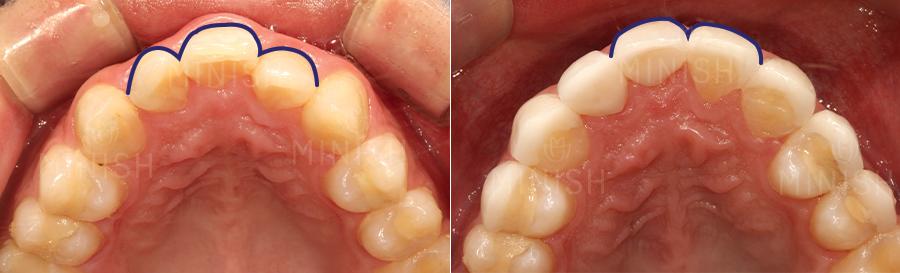

▼ 가평아들은 앞니 옆의 두 번째 치아(측절치)를 이용하여 결손된 앞니 한 개를 채워주었는데요.

기존 앞니와 잘 어우러질 수 있도록 잇몸 형태와 치아의 크기, 색상까지 여러 측면을 고려해 진행하였습니다. 그 중에서도 치은절제술 및 핑크미니쉬를 통해 잇몸 라인의 대칭을 맞춰주었는데요. 부어있던 잇몸이 빠른 시일 내 건강해질 수 있도록 함은 물론, 자연스러운 잇몸 형태로 개선이 되었습니다. 또한 교합 힘에 의해 잇몸이 내려가 있었던 부분도 핑크미니쉬로 하여금 연분홍빛 잇몸으로 개선되었고, 조화롭고 건강한 잇몸 형태를 띠게 되었습니다.

▼좁은 악궁과 #35번 결손치로 아랫니의 전체적인 배열도 삐뚤빼뚤한 양상을 보였습니다.

이 부분은 듀얼미니쉬로 개선을 진행하였는데요.

아랫니 전면을 틈새없이 코팅해주어 자연치아는 건강하게 보호해주면서 전체적인 치열이 고르게 배열된 것이 보이죠. 뿐만 아니라 색상과 질감까지도 개선되어 심미적으로도 한 층 좋아졌습니다.